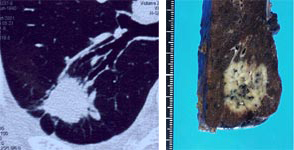

左写真が胸部CT写真です。黒いところが肺で、いびつで類円形な白い部分が肺がんです。

右写真が切除した標本の切離面で、茶色い部分が正常肺で、乳白色でゴマのように黒い点がある部分が肺がんです。